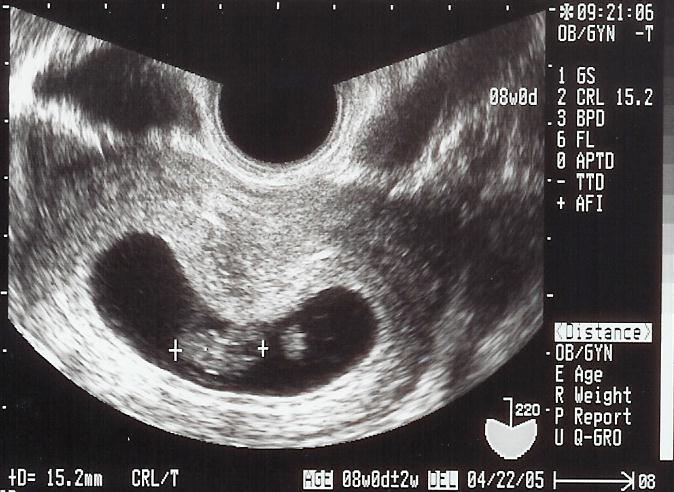

8週0日

15.2ミリになりました。

この日、shigeruの週数と予定日を決め、ママは婦人科から産科へ。助産師さんから「おめでとうございます」とこれからの説明をしてもらいました。そして、この病院でshigeruを産むことも話しましたよ。なぜなら、ママもこの病院で産まれたのですから。病院帰りに市役所で母子手帳をもらいました!!